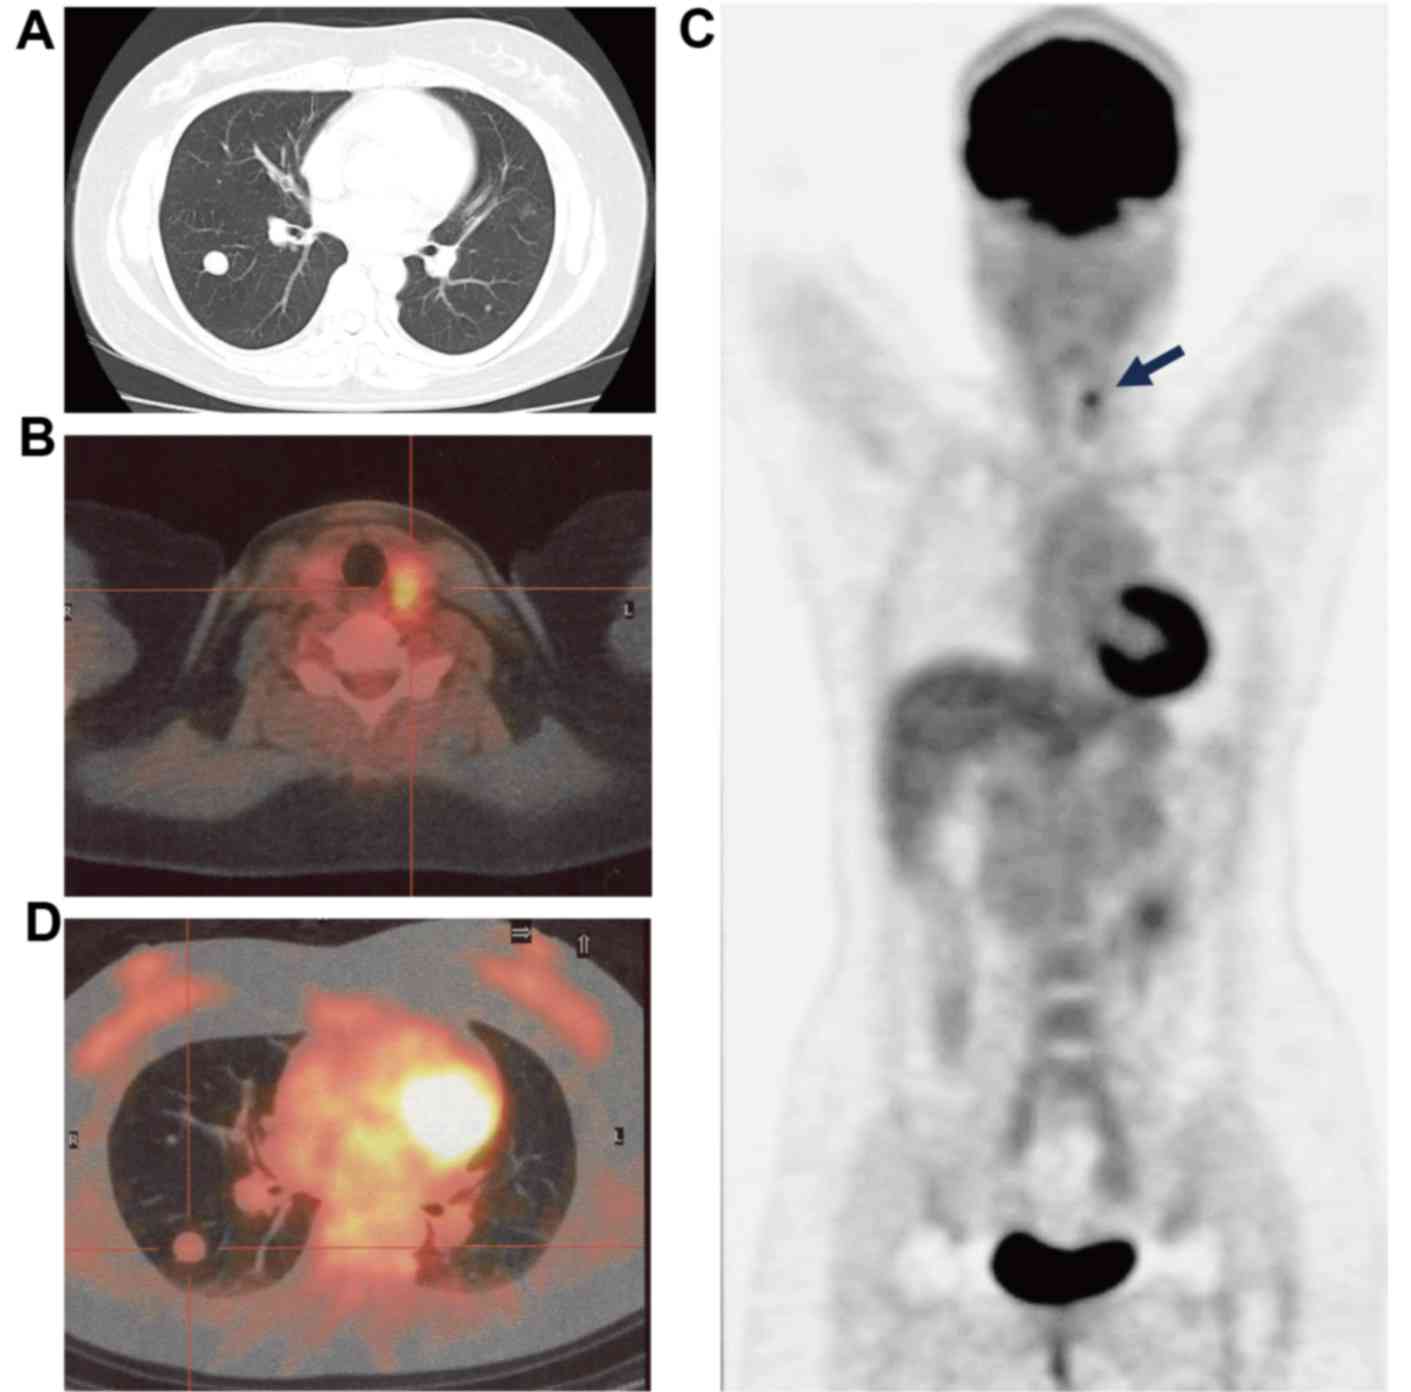

A 62-year-old post-menopausal female was referred to Kansai Medical University Takii Hospital for an investigation due to the presence of numerous pulmonary nodules detected in a routine chest radiography in August 2013. The patient had experienced bilateral upper back pain for two weeks prior to the first appointment at this hospital. The patient had no history of uterine myoma. A chest CT revealed the presence of a tumor in the right upper lung that was 60 mm in diameter and numerous nodular lesions of varying sizes in each of the lungs, in addition to a soft tissue mass that was 70 mm in diameter in the left second rib (Fig. 3A). The parameters assessed included complete blood count and standard clinical laboratory examinations, and the expression levels of specific tumor markers were within normal limits, including carcinoembryonic antigen, serum cytokeratin-19 fragments and Pro-gastrin-releasing pepetide. Contrast-enhanced magnetic resonance imaging of the head revealed a tumor in the left parietal lobe that was 20 mm in diameter, with an edema. As the patient was suspected to have a lung cancer with pulmonary, bone and brain metastases, an 18-FDG-PET/CT scan was performed. The results indicated abnormally high 18-FDG uptake in the right upper lung tumor, the left third rib tumor, atlas vertebra, fourth thoracic vertebra, bilateral ilia and multiple bilateral pulmonary nodules in the lungs (Fig. 3B-D; SUVmax, 20.1). Subsequently, a CT-guided needle biopsy of the right upper lung tumor was performed. Histological examination of the lung biopsy tissue specimen revealed a disordered arrangement of spindle-shaped tumor cells with mild atypia (Fig. 2D). Immunohistochemical examination revealed that the cells stained positive for α-SMA (Fig. 2E). By contrast, CD34, S-100, estrogen receptor (ER) and progesterone receptor (PgR) expression was not detected in these cells. The Ki-67 ratio was <1% (Fig. 2F). These findings are consistent with the phenotypic characteristics of benign leiomyoma. In order to confirm the pathological diagnosis, an additional CT-guided needle biopsy of the tumor of the left rib was performed. The results of the second biopsy tissue specimen from the tumor of the left rib corroborated the findings from the first biopsy specimen obtained from the tumor in the right lung. Consequently, a definitive diagnosis of PBML was established. The patient received whole brain irradiation followed by palliative irradiation for the pulmonary nodules in the right upper lung and left second rib. However, no treatment response was observed and the tumors were identified to be growing (Fig. 4). After three months, the patient was re-admitted to hospital due to a consciousness disorder. Corticosteroids and glycerin were administered, and the neurological symptoms were temporarily improved. However, the patient succumbed to septicemia with Clostridium perfringens.

Figure 3.

Radiological findings for case 2. (A) The image of CT for pulmonary nodule. (B) The fusion image of 18-FDG-PET/CT in horizontal plane. The left pulmonary nodule exhibited a notably high 18-FDG uptake (SUVmax, >20.1). The right pleural thickening also demonstrated marked 18-FDG uptake (SUVmax, >10.1). (C) A lesion exhibiting high 18-FDG uptake (SUVmax, >12.1) was detected in the right side of the atlas vertebra. (D) The fusion image of 18-FDG-PET/CT in the coronal plane. Numerous lesions had a positive accumulation of 18-FDG (arrows). CT, computed tomography; 18-FDG-PET/CT, 2-deoxy-2-(fluorine-18)-fluoro-D-glucose positron emission tomography/CT; SUVmax, maximum standard uptake value.